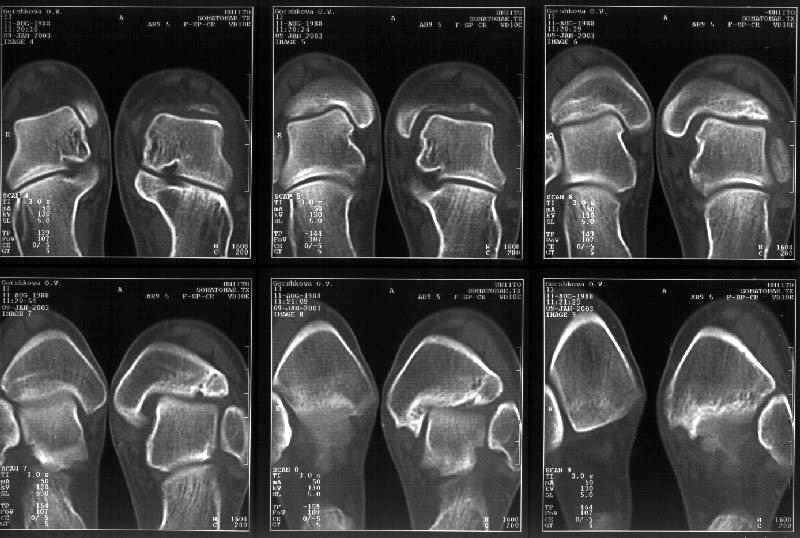

На следующий день пациентке сделали КТ. Может быть, после просмотра картинки будут другие предложения? Не убрать ли ве-таки этот фрагмент

позади внутренней лодыжки, который оттесняет таран кнаружи?

Думаю, КТ прочитан не верно. Задняя часть медиального маллеола, в сущности уже часть заднего маллеола стоит на месте и трогать её не следует. Передняя часть маллеола на 3-4 мм удалена от тарана. Сравните с пространством между

латеральным маллеолом и тараном. В норме все три должны быть одинаковы: между тараном и латеральным, задним и медиальным. Это главное условие устойчивого сидения тарана в голеностопном суставе.

Все-таки она как раз была была отколота и вместе с тараном смещена латерально.

Внутренняя лодыжка не была сломана, она как была на своем месте, так там и находится. Это таран от нее отдавлен кнаружи смщенным в его сторону фрагментом позади внутренней лодыжки. За счет чего и есть проявления нестабильности связок.

Мне в тоже время совершенно ясно видно по той же КТ, по 4 срезам, расположенным в центре и вверху пленки, что перелома внутренней лодыжки не было, в следующем собщении я приложу увеличенный фрагмент томограммы. А к этому письму прилагаю увеличеный фрагмент послеоперационной рентгенограммы, где выделил отколотый фрагмент

позади внутренней лодыжки. И он, как я вижу, находится между стержнем и тараном. А перелома внутренней лодыжки, и тем более смещения, IMHO

не определяется.

Отправитель: Alexander Chelnokov 12 Январь 2003, 14:55

Здесь 4 среза, начиная от основания лодыжки и проксимальнее. Где, по Вашему мнению, проходит линия перелома, отделяющая переднюю часть внутренней лодыжки от большеберцовой кости? Заранее спасибо.

Я пометил линию перелома черной линией.

К сожалению на последних присланных срезах КТ нет более низкого, через таран, среза, который был на прежнем майле. На XR я попытался показать

стержень внутри сустава и то как он раскрывает пространство между тараном и мед. малеолом.